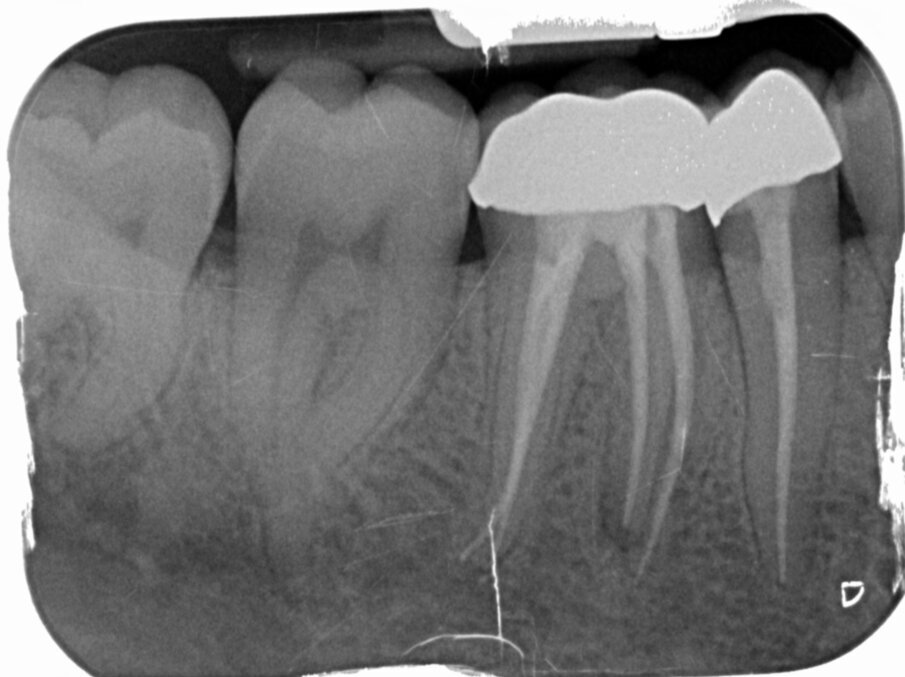

Vier jaar later bezoekt de patiënt wederom op verwijzing onze praktijk. Hij ondervindt wat ongemak van element 46 waar de tandarts 3 jaar geleden een kroon op heeft gemaakt. Bij kauwen is het element iets pijnlijk, iets wat hem sinds twee maanden opgevallen is. Afbeelding 5, 6 en 7 kunnen bevestigen wat de oorzaak is: Een opspelende laesie van endodontische origine (LEO) aan de mesio-buccale radix. Bittere teleurstelling aan onze zijde en een verdrietige patiënt.

Mesiobuccaal en mesiolinguaal ontdoen we de kanalen van de Thermafil-carrier en de achtergebleven guttapercha. Een glijbaan hadden we vier jaar geleden ook, dus dit deel van de behandeling blijft redelijk eenvoudig. Het is vooral belangrijk geduldig te blijven en net zo lang de oplosmiddelen voor guttapercha in te laten werken en te activeren dat de paperpoints die we gebruiken om de oplosmiddelen weer op te deppen er brandschoon uitkomen (afbeelding 13). Deze keer geen Thermafil, maar de Squirt-techniek waarbij we guttapercha direct in de kanalen spuiten (afbeelding 14 en 15).

De eindfoto’s zijn duidelijk: een iets vollere shape en wat nadrukkelijkere puffs. Fingers crossed! Over drie maanden weten we meer.